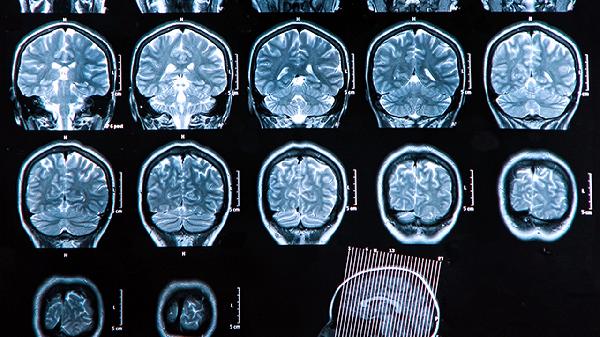

对于超声可疑病例,建议行胎儿MRI检查最佳孕周30-34周。MRI能更精准评估脑回发育、髓鞘化程度及是否存在无脑回畸形等皮质发育异常,对病因鉴别有重要价值。